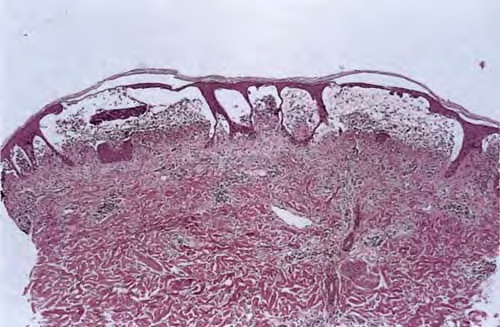

Histopathology

. The typical histologic features are best observed in erythematous skin adjacent to early blisters. In these zones, neutrophils accumulate at the tips of dermal papillae. With an increase in size to microabscesses, a significant admixture of eosinophils may be noted. As microabscesses form, a separation develops between the tips of the dermal papillae and the overlying epidermis; thus, the early blisters are multiloculated . The presence of fibrin in the papillae may give them a bluish appearance. Within 1 to 2 days, the rete ridges lose their attachment to the dermis, and the blisters then become unilocular  and clinically apparent. At this time, the characteristic papillary microabscesses may be observed at the blister periphery. For this reason, the inclusion of perivesicular skin in the biopsy specimen is of

utmost value. The papillary dermis beneath the papillae may have a relatively intense inflammatory infiltrate of neutrophils and some eosinophils. Many neutrophils may exhibit leukocytoclasis. Subjacent to this, a perivascular infiltrate composed of lymphocytes, neutrophils, and eosinophils may be apparent. the diagnostic finding of papillary microabscesses may not be present in all patients. Apoptotic keratinocytes may be noted above the papillary microabscesses.